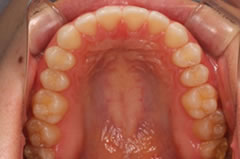

ワイヤーやブラケットなど従来の矯正装置を使用せず、治療段階ごとに少しずつ形状の違う透明なマウスピースを定期的に交換して歯を動かしていく矯正方法です。

治療のステップごとに歯の移動量を測定して次のステップのマウスピースを作製し、硬さや厚みの違うマウスピースに交換しながら矯正力をコントロールして、少しずつ理想的な歯並びへと歯を動かしていきます。

「アソアライナー」は、軽度のでこぼこや歯の隙間、矯正後の後戻りなど、比較的軽い症状の不正咬合に適応しており、抜歯を必要とする症状や奥歯など全体的に歯を動かす矯正には適応していません。

マウスピースは、歯茎まで覆う深型の形状で、当初は異物感を感じるかもしれませんが、すぐに慣れると思います。